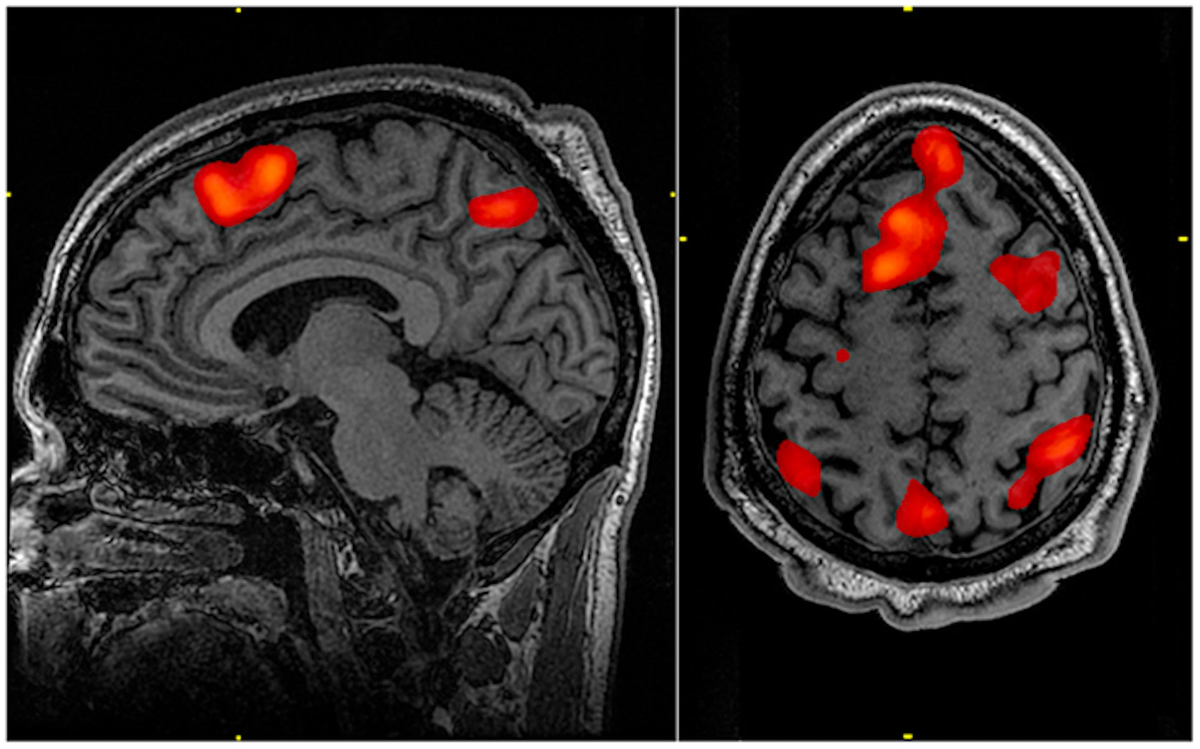

В наше время наука развивается с огромной скоростью, и многие открытия, которые раньше казались фантастическими, сегодня стали реальностью. Одной из таких технологий является фМРТ (функциональная магнитно-резонансная томография), которая позволяет изучать работу мозга в реальном времени и декодировать мысли человека(об этом чуть дальше ;))

ФМРТ - это метод медицинской визуализации, который позволяет получать изображения мозга с высоким разрешением. Этот метод использует магнитные поля для создания изображений мозга, которые затем могут быть обработаны нейросетями для декодирования мыслей человека.

Одним из примеров использования фМРТ и нейросети является исследование, проведенное в Университете Торонто и Техаса. В этом исследовании ученые использовали фМРТ для измерения активности мозга человека и распознавания его мыслей. Затем эти данные были переданы нейросети, которая смогла выделить закономерности в работе мозга и декодировать мысли. Однако - тогда это было декодирование исключительно в текст.